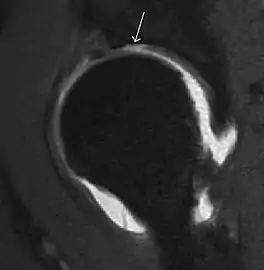

Most of the angles and measurements described in the plain radiograph section can be accurately reproduced on MRI. In addition, the superiority of MRI resolution with intra-articular contrast allows detection of labral and chondral abnormalities that may influence the choice of medical, percutaneous, or surgical management (Figure 9).[1]

Figure 9:

MR arthrography has proven superior in accuracy when compared to native MR imaging. It is considered the best technique to assess the labrum. Knowledge of the normal variable morphology of the labrum helps to differentiate tears from normal variants. A triangular shape is most commonly seen in 66% of asymptomatic volunteers, but round, flattened, and absent labra can also be found in asymptomatic populations. MR arthrography has demonstrated sensitivity over 90% and specificity close to 100% in detecting labral tears. Loose bodies are demonstrated as filling defects surrounded by the hyperintense gadolinium.[1]

Association between labral tears and chondral damage has been demonstrated. This underscores the interaction between cartilage and labrum damage in the progression of osteoarthritis. Chondral damage to the posteroinferior part of the acetabulum as a contrecoup lesion occurs in approximately one-third of pincer cases secondary to persistent abutment on the anterior part of the joint leading to a slight posteroinferior subluxation. This is considered a bad prognosis sign.[1]

MR arthrography can also demonstrate ligamentum teres rupture or capsular laxity, which are debated causes of microinstability of the hip. Elongation of the capsule or injury to the iliofemoral ligament or labrum may be secondary to microtrauma in athletes. MR can demonstrate abnormalities in these cases, such as increased joint volume or a ligamentum teres tear (Figure 9).[1]